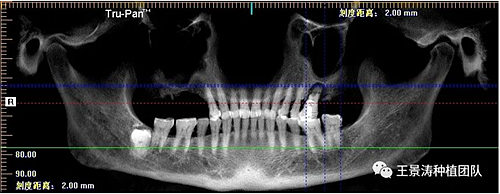

左側(cè)下頜第二磨牙及右側(cè)下頜第一磨牙同時(shí)即刻種植病例?;颊吣贻p女性,無系統(tǒng)性疾病。37及46殘冠及殘根,且46劈裂,無法冠修復(fù),必須拔除。37根尖慢性炎癥,大量肉芽組織存在,46根分叉較高,根分叉骨質(zhì)尚可。CBCT示:根尖骨質(zhì)至下牙槽神經(jīng)管距離可滿足種植體的初期穩(wěn)定性,遂考慮即刻種植,并在種植體周邊填入骨粉并覆蓋骨膜,雙側(cè)的種植體初期穩(wěn)定性相差無幾,但考慮到37根尖慢性炎癥較大,遂給予埋入式種植。